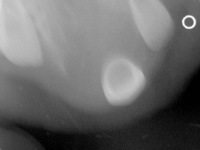

At the time of presentation in the dental department at BCCH, the infant appeared to be otherwise healthy and in no distress. Intraoral examination revealed a firm, smooth mass, 1.5 cm by 2 cm by 3 cm, in the anterior left maxilla (Fig. 1). Tooth 61 was the only tooth visible clinically; it was non-carious and extremely mobile within the enlarged mass. Expansion of the mass was primarily labial, although it was also palpable from the palatal aspect. Despite being nonerythematous, nonpurulent, nonpulsatile and immobile, the mass had a distinct bluish-purple tinge. Palpation of the mass appeared to be uncomfortable for the infant. Distortion of the upper lip and left nasal ala was noted, along with interference with mouth closing (Fig. 2). The tumour did not appear to cross the midline. Radiographic imaging of the premaxilla area revealed an expansile radiolucency with poorly defined margins. Displacement of the developing teeth 51, 62 and 61 within the radiolucency gave the teeth a "floating" appearance (Fig. 3). VMA testing was not carried out, as the infant's difficulty in feeding, the risk of progressive airway compromise and his parents' apprehension made the need for surgery urgent.